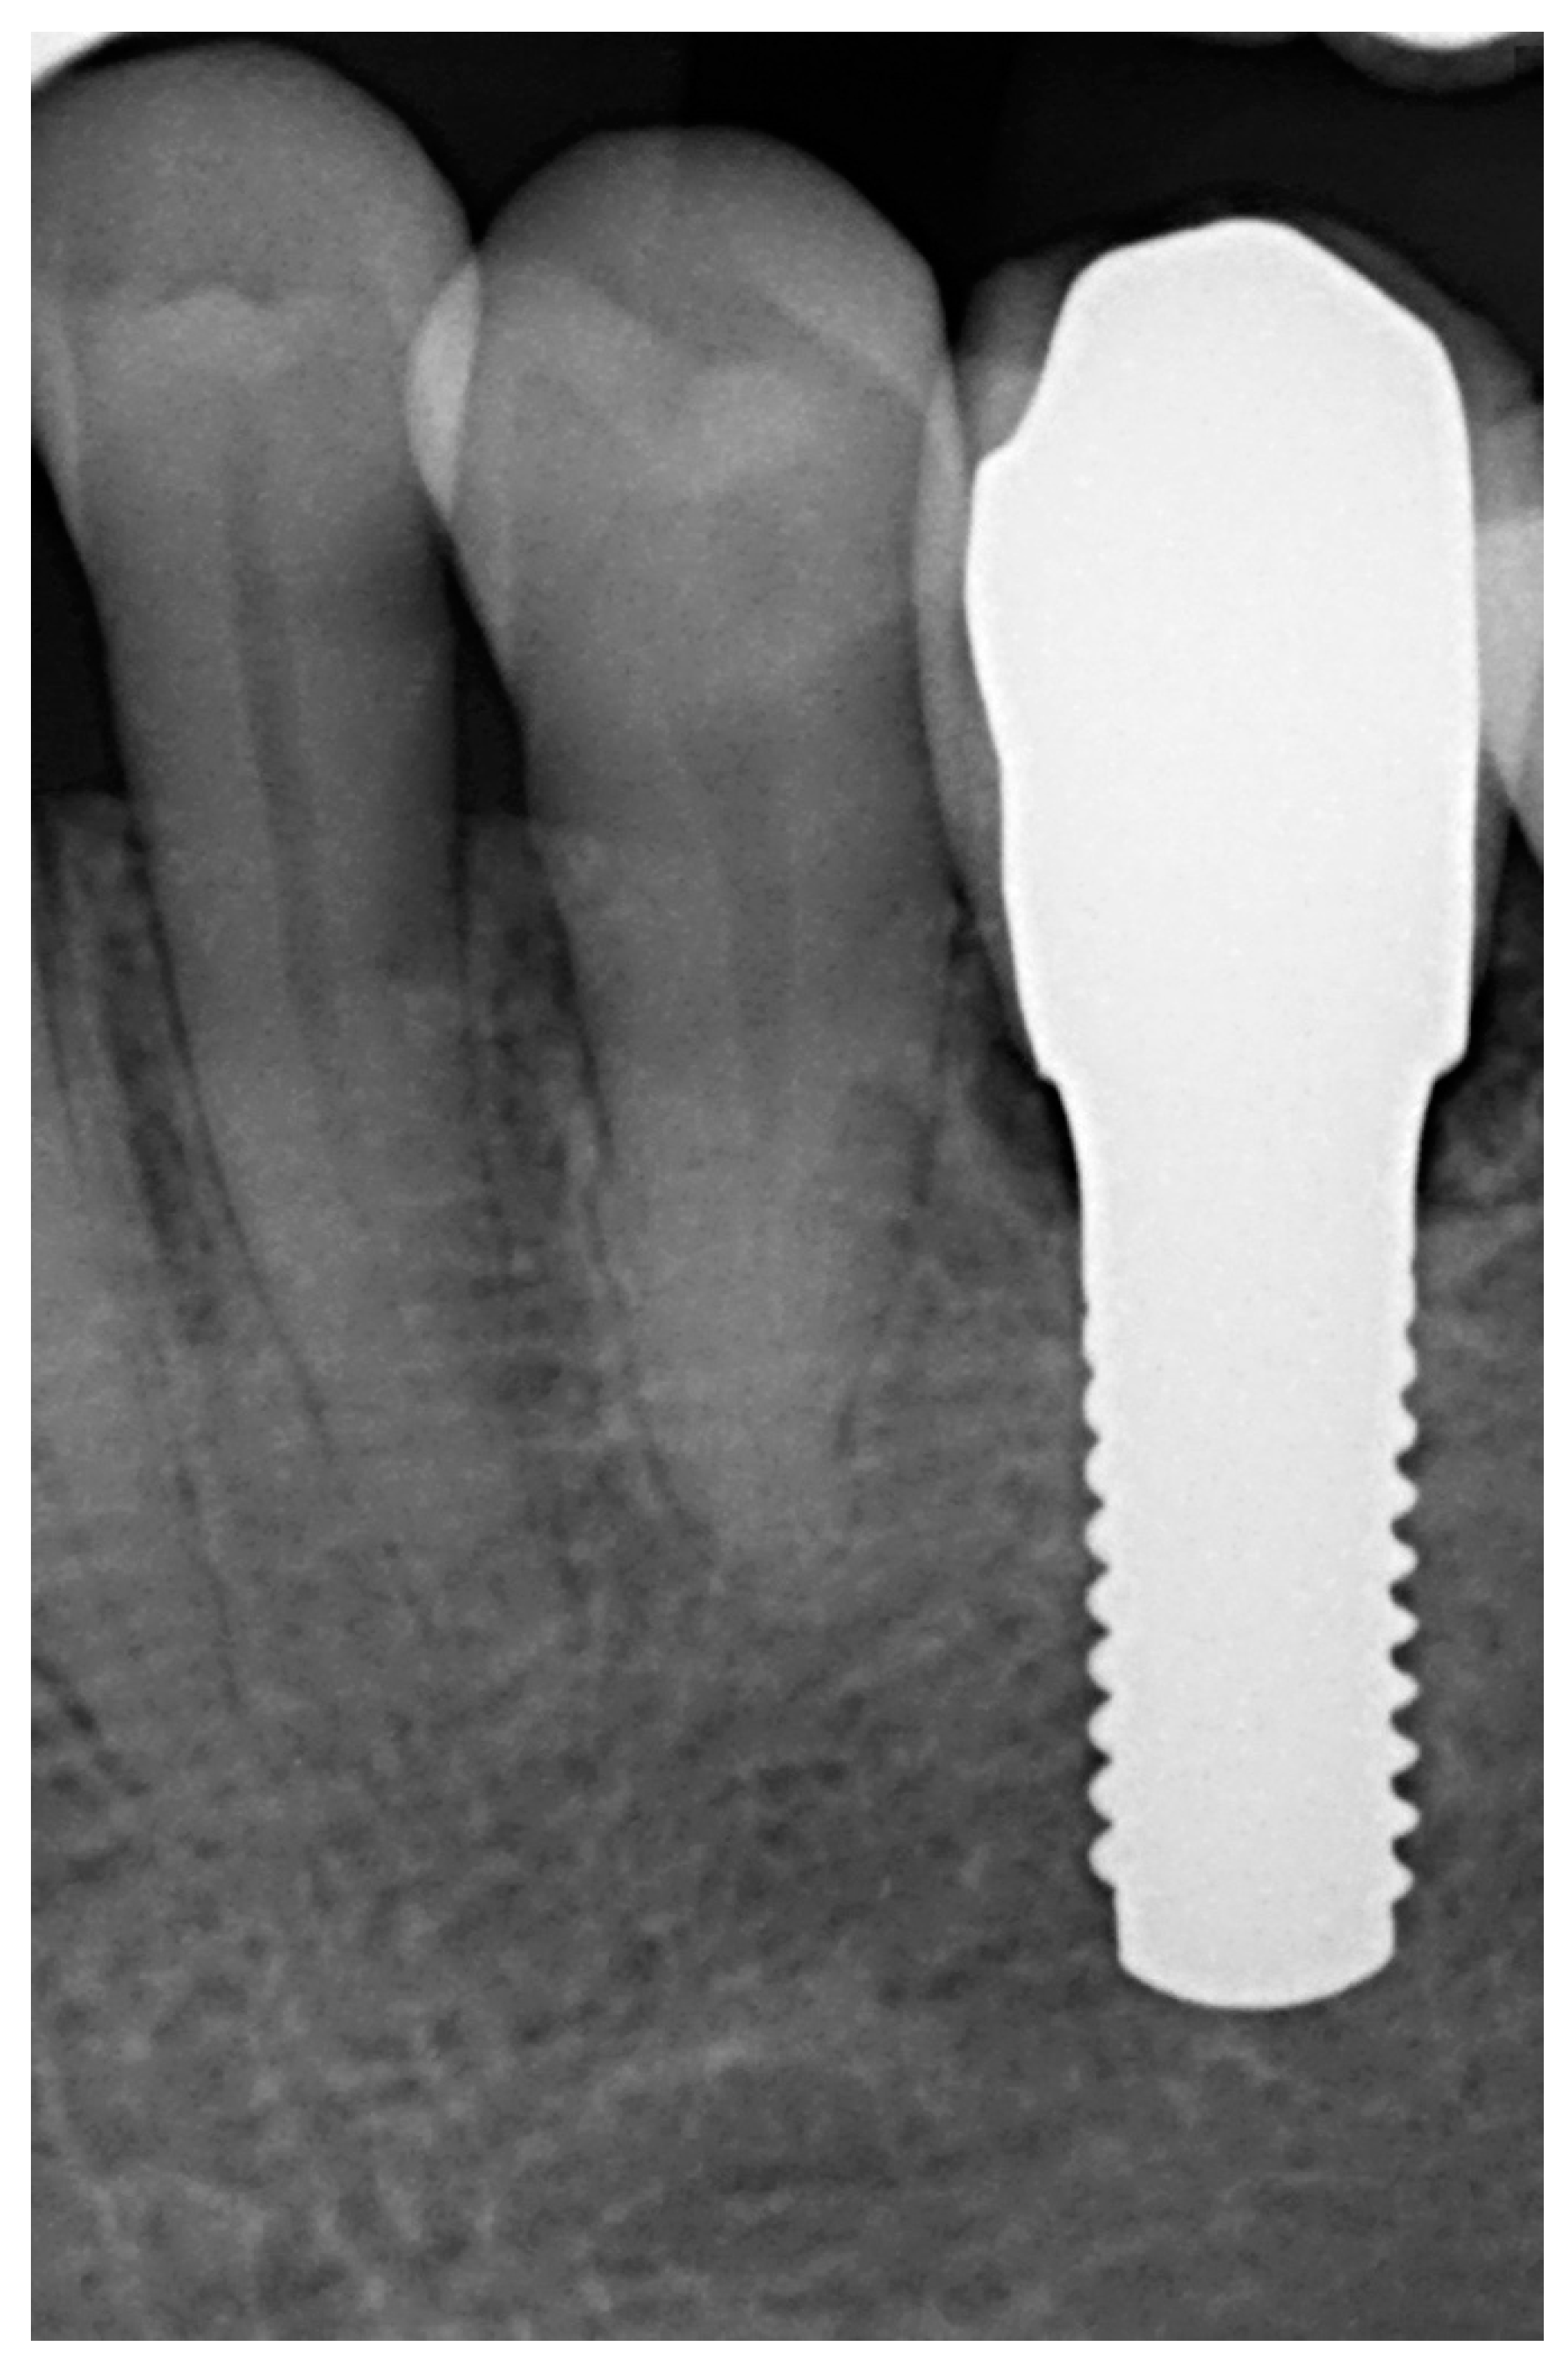

Afterwards, GBR procedures were performed if needed, a plastic abutment protector was placed, and flaps were closed with single sutures to ensure transmucosal implant healing. An intraoral radiograph was taken immediately after surgery (Figure 3). Postoperative medication was then prescribed in the form of amoxicillin 500 mg (or clindamycin 300 mg in patients allergic to penicillin) every 8 h for 7 days, ibuprofen 600 mg every 8 h for four days, and chlorhexidine rinses twice a day for 15 days.

Figure 3. Immediate postoperative intraoral X-ray view after one-piece zirconia implant placement.